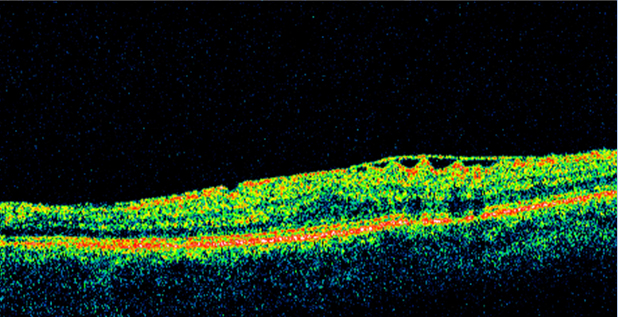

High-resolution OCT has become increasingly helpful in the diagnosis and management of ERM as it can allow for both 3-dimensional and cross-section evaluation of the macula. On an OCT image, ERM appears as a hyperreflective linear band on the inner retina. OCT can detect subtle ERMs as well as those associated with macular edema or other macular pathology. Some patients with ERM may have foveoschisis, a separation of the outer nuclear layer from the outer plexiform layer.[4]

OCT can also help guide patient management. Some cases of ERM with vitreomacular traction are subtle clinically and may be more easily detected with OCT. One of the great advantages of OCT is the assessment of the vitreoretinal interface. This can provide additional information regarding therapeutic options and prognosis. In surgical cases, evaluation of each scan can elucidate the best approach for removal. Spectral-domain OCT can help evaluate the outer retinal layers/structure, which may have bearing on the physiologic outcome after an ERM removal.